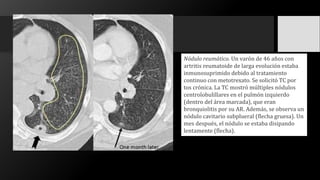

Nódulo reumático. Un varón de 46 años con

artritis reumatoide de larga evolución estaba

inmunosuprimido debido al tratamiento

continuo con metotrexato. Se solicitó TC por

tos crónica. La TC mostró múltiples nódulos

centrolobulillares en el pulmón izquierdo

(dentro del área marcada), que eran

bronquiolitis por su AR. Además, se observa un

nódulo cavitario subplueral (flecha gruesa). Un

mes después, el nódulo se estaba disipando

lentamente (flecha).